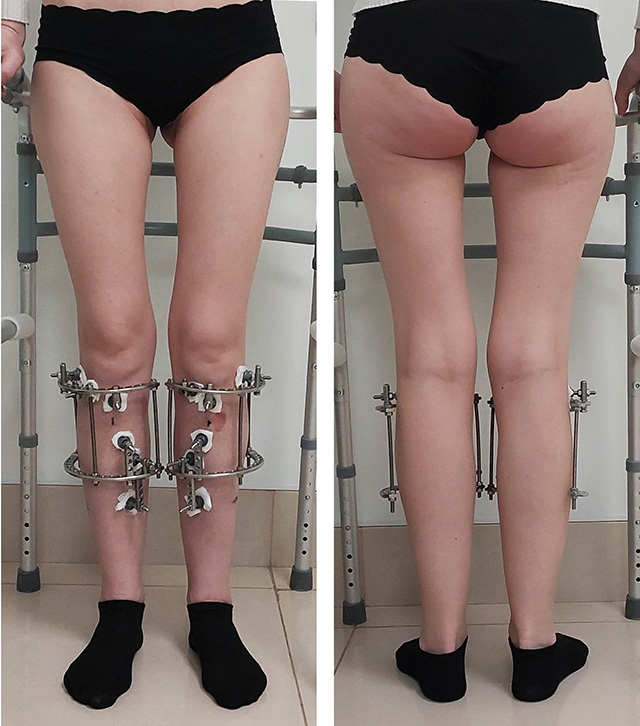

ЖЕНЩИНА 34 ЛЕТ. ВАРУСНАЯ (О-ОБРАЗАНЯ) ДЕФОРМАЦИЯ НОГ

Внешний вид до коррекции. Такая кривизна ног выходит за рамки эстетической (косметической) проблемы. Баланс нагрузок в коленном суставе нарушен. Молодость и здоровье пока компенсируют проблему, однако уже на протяжении нескольких последних лет появились жалобы на ноющие неприятные ощущения после нагрузок.

Внешний вид ног в процессе фиксации. В данном случае использовали мини-фиксаторы. Это облегченный вариант аппарата Илизарова.